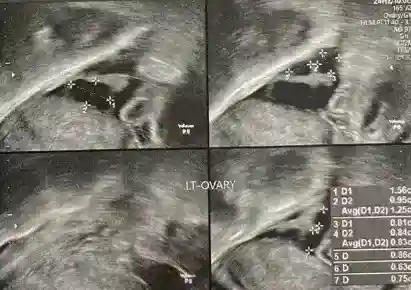

▫️卵巢功能 AMH 仅 1.28ng/ml(低于正常值)

2️⃣ 卵巢反应差(初始促排仅获 4 枚卵)